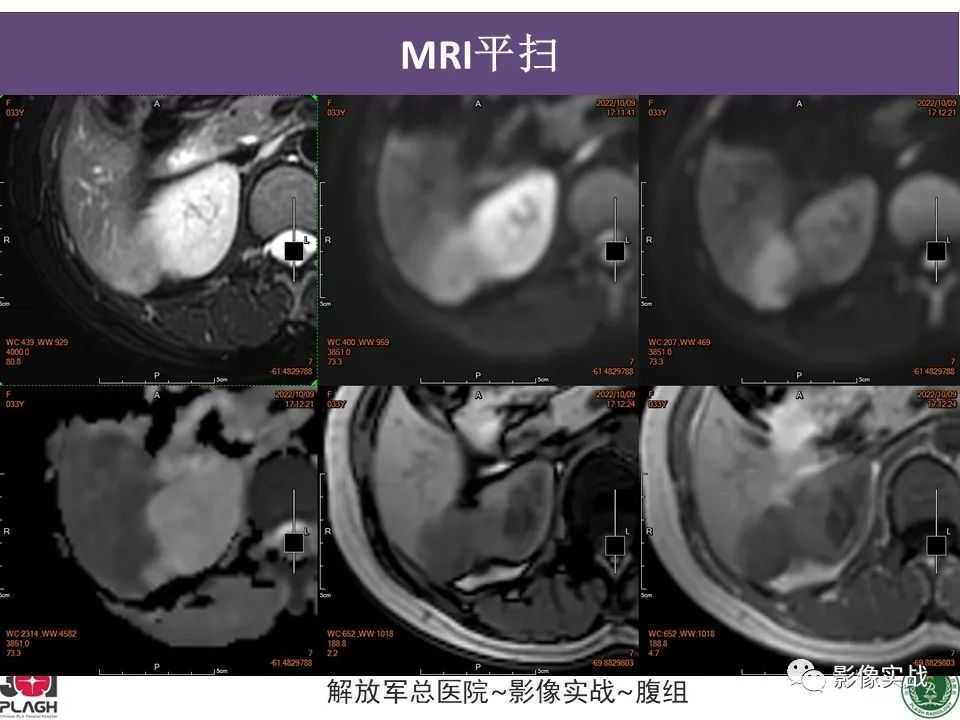

肝内胆管细胞癌1例MR影像

【病例】肝内胆管细胞癌1例MR影像-1